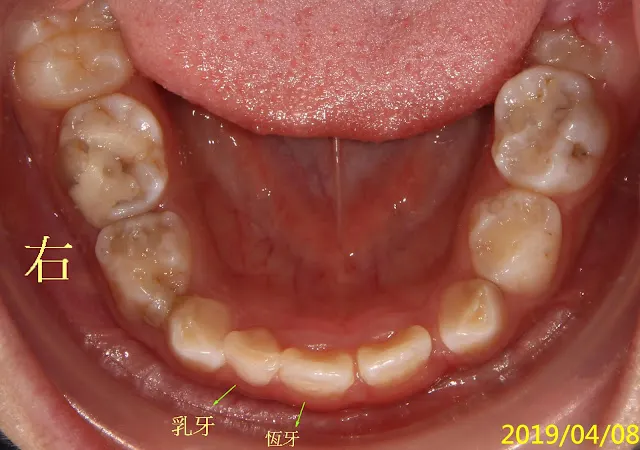

最後總結一下在此圖(謝謝這位小朋友的配合演出),剛好可以讓您看到我剛剛講的乳牙、恆牙大小問題是指什麼,以及上面那個男醫師所說的恆牙一開始會在乳牙內側長出是正常的,通常幾個月後,啥事都不用做,光靠軟組織舌頭的力量(再一次也應證功能性矯正的理論基礎),就會把它推出去排好歸隊了。別緊張,請稍安勿躁,再觀察。

弟弟那顆牙是第一乳臼齒,大約是在這年紀換沒錯,但有時恆牙會從別的方向長出(正常是正下方),如弟弟的情況,換牙不會那麼順,會慢慢像沉船傾倒歪一邊,以後長出來的恆牙也會是歪的,但,大多數會被舌頭等軟組織自動推回去(如我文中所述,不同者是文中是以下前牙為例),不一定需矯正,再觀察即可(意思是沒事也要來半年定檢)。 此時拔掉確實有可能會避開長歪(也有可能根本避不開),但我不想做無謂之事(這一定是要打針上麻的,不是像前牙可拈花微笑擦擦表面麻醉藥膏就夠了),因為這本來就有可能自己會掉、自己會長好,無需人為的介入,如我文中所言。